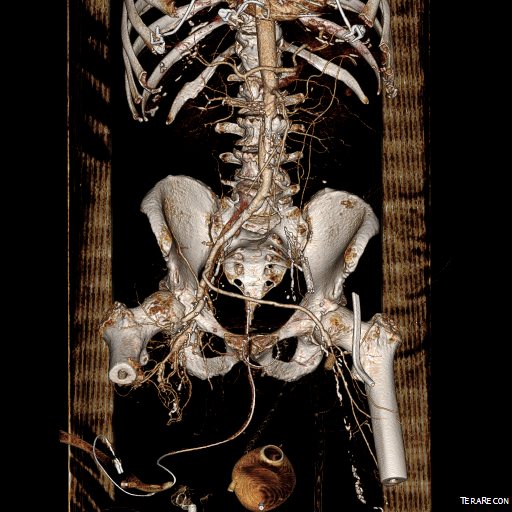

Let me show you one of the first cases I did after returning to Cleveland. I am now practicing at Fairview and Avon Hospitals, premier flagship hospitals in the Cleveland Clinic fleet, on Cleveland’s west side, and a patient arrived while I was on call with sudden onset of pain in his leg from a lack of blood flow. He had occlusive atherosclerotic plaque extending from his external iliac artery to the above knee popliteal artery causing ischemic rest pain.

I contacted LeMaitre Vascular and got in touch with your representative, L. Fisher, who promptly sent the Moll Ring Cutters I needed to perform a remote endarterectomy of the patient’s occlusive external iliac and superficial femoral artery plaque. The technical details of remote endarterectomy are have been covered in my blog (https://vascsurg.me/?s=endore), but in the end, through a 7cm incision in the groin (don’t believe the hype, this is minimally invasive), I restored his arteries to their original open condition. Shown below are the results. It was with great sadness that I heard that the LeMaitre Vascular equipment being sent were the last of the stock available in North America. The patient did very well, with the operation completed well before lunch, and is recovering rapidly from his small wound and big rescue. He gets to walk out of the hospital on two legs, but also with the surety that he avoided a major bypass operation, and avoided the short term gains of stenting from the aorta to the profunda -more peel packs and landfill items and a dubious long term durability. Hey, I even used a XenoSure patch on the common femoral.